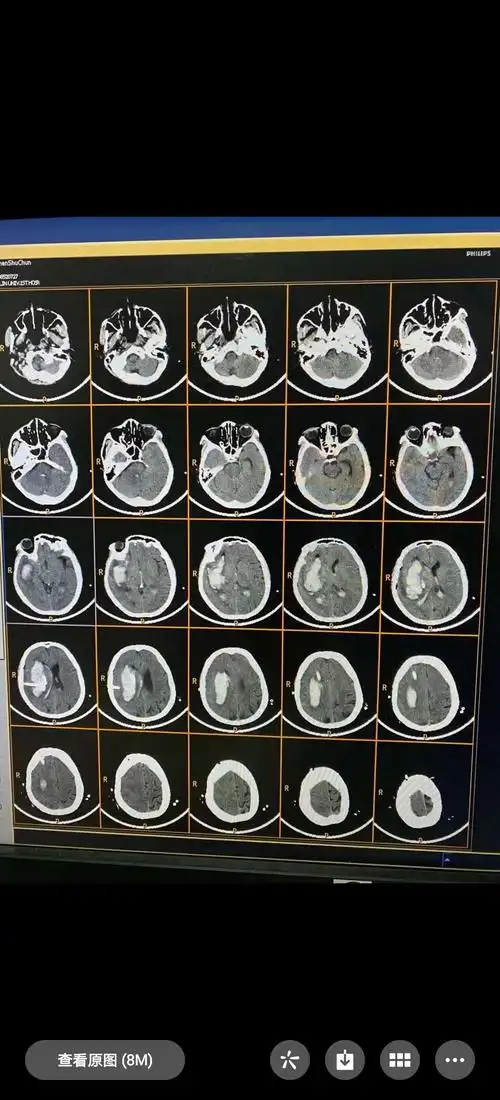

患者:沈淑春,女,60岁,右侧基底节区脑出血,呈嗜睡状态